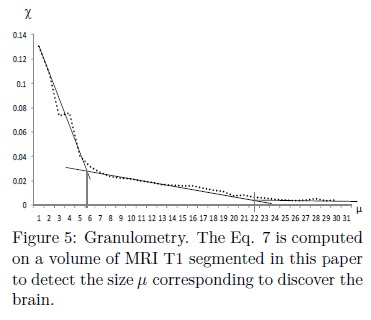

where vol represents the volume of f, i.e., the sum of all intensity levels into the image. Figure 5 presents a granulometric study applied on a volume of MRI T1 segmented in this paper. Notice in this figure that, for sizes of μ between 1-5 the openings detect a component corresponding to the skull while openings between sizes μ in the interval 5-21 detect an important presence of the brain. From this analysis, appropiated sizes of μ to detect the marker of the brain using the morphological opening are within the interval μ ∈ [6, 22].

μy (f) used to obtain an initial marker of the volume f. According to the granulometric study presented in Fig. 5 (see section Granulometry), adequate sizes for μy are contained in the interval μy ∈ [6, 22]. In particular, in this paper, μy= 12 is utilized.

iii. The selected size of the opening to obtain a marker is μy= 12. This value belongs to the interval 6 to 22 according to the graph in Fig. 5.